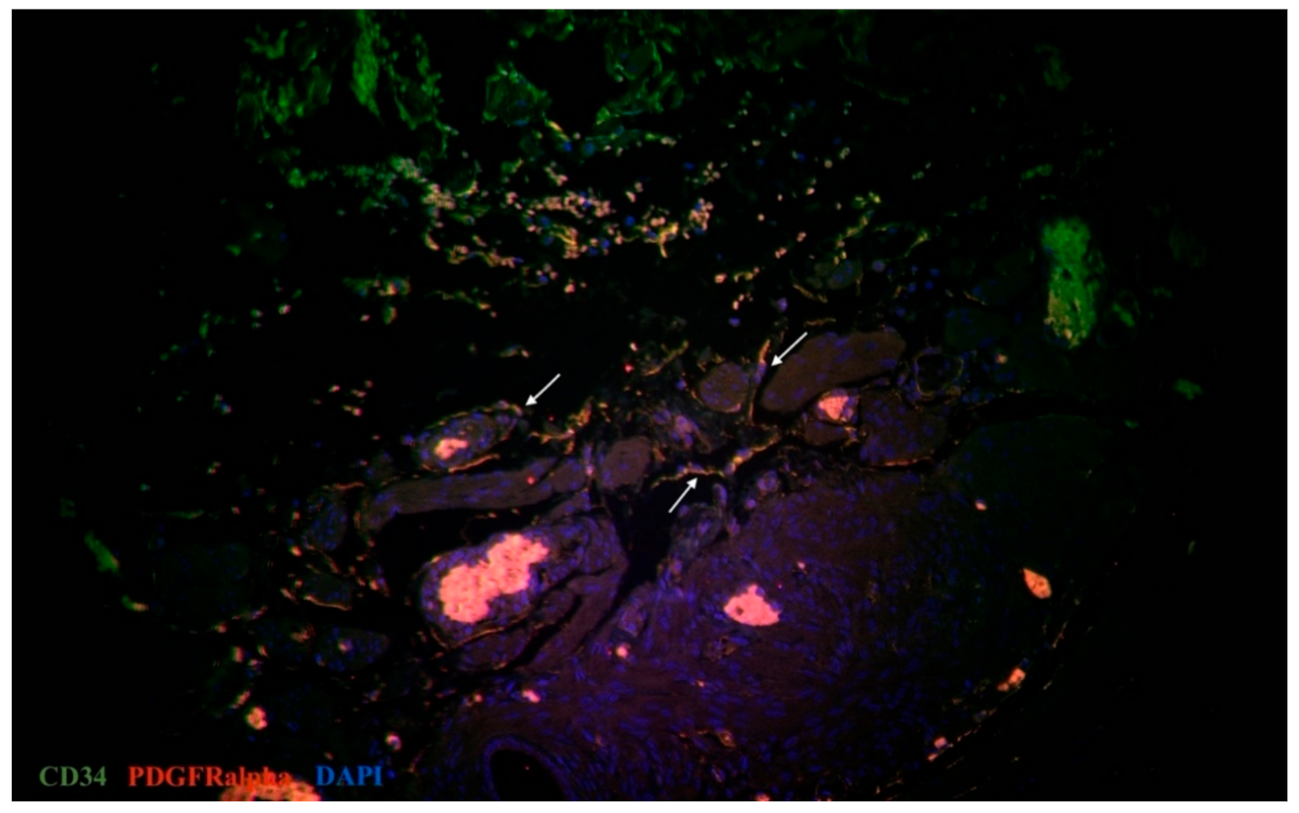

3.2. IHC Analysis of Telocytes in the Fallopian Tubes

- Cretoiu, S.M. Immunohistochemistry of Telocytes in the Uterus and Fallopian Tubes. Telocytes 2016, 913, 335–357. [Google Scholar] [CrossRef]